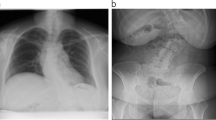

Case 2

A 34 year-old pregnant patient (gestational age 19 weeks) presented in the outpatient emergency department with progressive genital hypoesthesia and incomplete paraplegia of the lower extremities. An MRI revealed an intramedullary tumor at Th10/11 (Fig. 2), which was biopsied through a hemilaminectomy at Th10-Th11 (surgery duration 198 min, TIVA anesthesia) in prone position. Histopathology detected a WHO grade II ependymoma; therefore, the indication for a tumor resection was taken. The patient underwent an uneventful gross total resection 1 week later (surgery duration 165 min, TIVA anesthesia, intraoperative neuromonitoring with motor evoked potentials). No perioperative complications occurred and the patient gave birth at 33 weeks (birth weight 2990 g). The incomplete paraplegia improved at follow-up after 5 years to a minor paresis of the left leg.